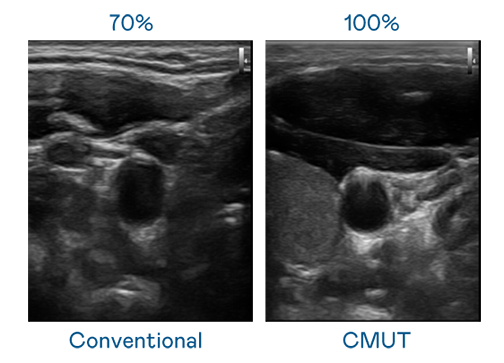

CMUT 技术是一种用电容式微机电元件来产生超音波讯号的技术。与传统 PZT 压电式技术相比,CMUT 频宽增加 30%,更宽频的超音波讯号让影像解析度大幅提升,是实现高影像品质医疗超音波扫描、促进精准医疗发展的关键技术。

大频宽带来超清晰影像

超音波影像的解析度高低,首先取决于探头能发出的讯号频宽。九洲国际 CMUT 可提供高清晰的超音波讯号,提供高频宽、高灵敏度、影像纹理细节更高的超音波影像,协助医护人员缩短影像判读时间及利用精准的医疗影像进行诊断。